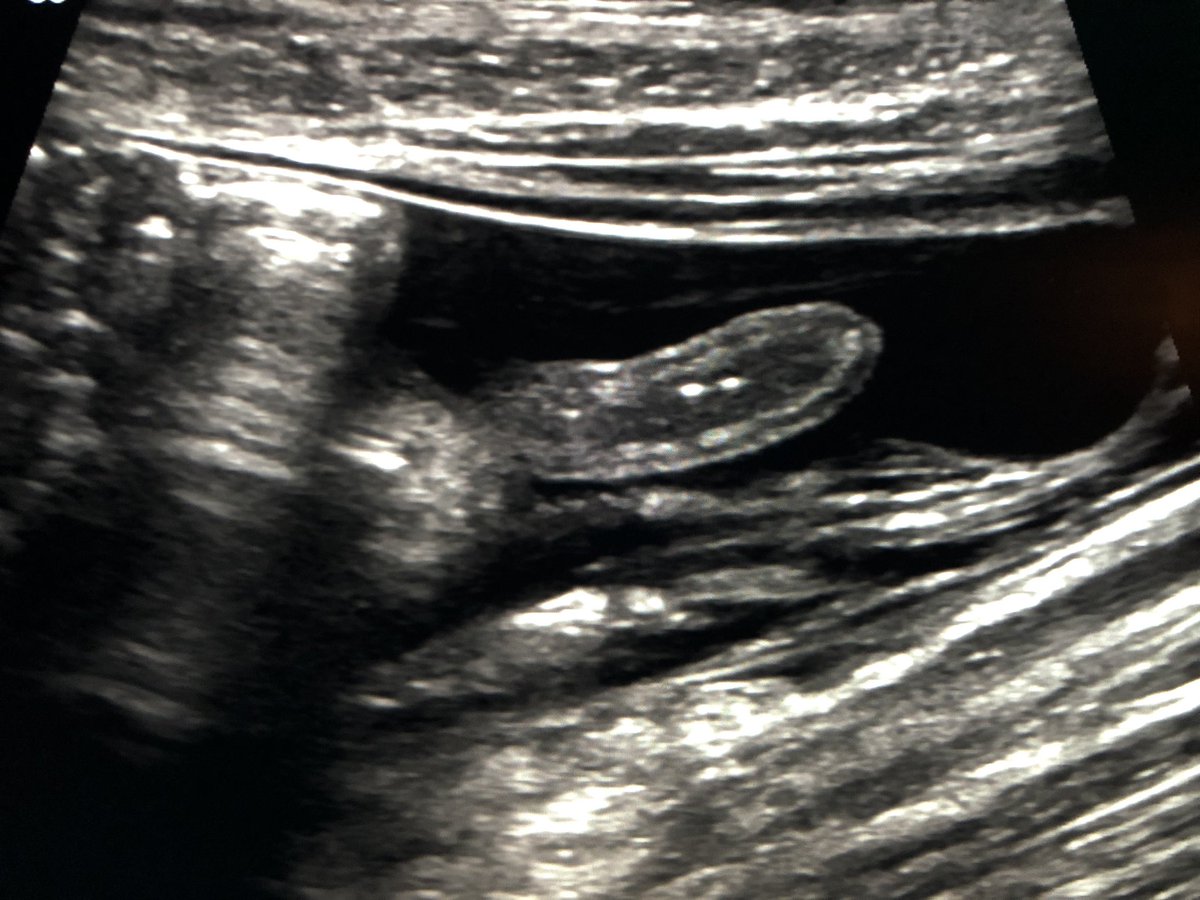

Good call guys. This is the patient after 10 minutes in the left lateral decubitus position.pic.twitter.com/emQBPMXFV2

Prikaži ovu nitHvala. Twitter će to iskoristiti za poboljšanje vaše vremenske crte. PoništiPoništi -